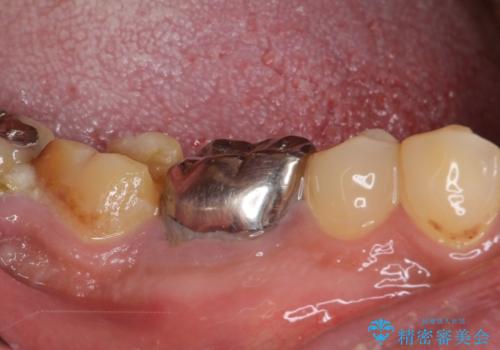

- 親知らずを抜くことが怖く、先送りにした結果親知らずの前の歯に大きな虫歯ができてしまったとのことで来院された患者様です。

親知らずは速やかに抜歯し、手前の歯とその前の歯に歯槽骨にまで及んだ虫歯が認められたため、歯槽骨を削るなどの歯周外科処置を行うこととしました。

歯周外科処置は、術後に痛みを感じたり、歯肉の状態が落ち着くまで歯がしみたりと苦痛を伴いますが、適用となる場合には抜歯を回避する手段として大変有効です。